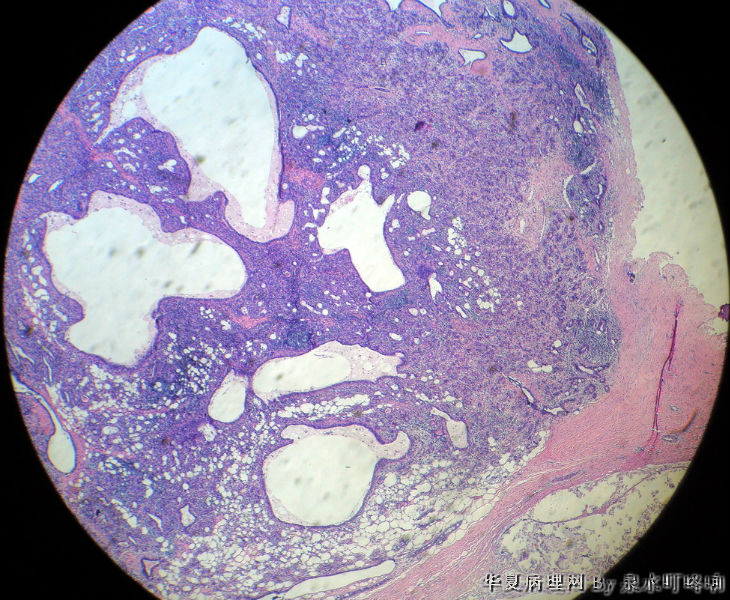

120213,女,23岁,右乳腺肿物半年,术中见肿物为多房性囊性肿物,内容黄色粘稠液体。

大体:灰白囊性肿物一个,大小约3×2×1.9厘米,局部囊壁增厚。

低倍小叶结构存在,炎细胞,导管扩张=炎症,考虑导管扩张症。

1.图像中有囊性增生,2.有腺病的结构,3.同时在低倍中可以看到有瘤样的结构,高倍中以腺肌上皮增生为主,未见核分裂,也未见恶性的现象,因此诊断乳腺的腺病瘤更为合适。

淋巴细胞性乳腺炎并导管扩张性囊性变。

乳腺小叶炎症导致小叶结构发生变形,有的腺泡萎缩,有的导管扩张,间质内淋巴细胞、纤维组织增生,都是炎症性适应性病变。